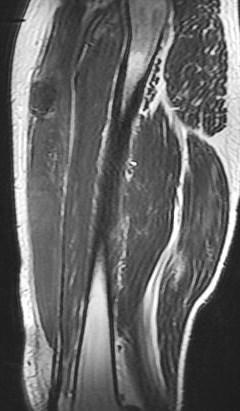

25 y/o work injury, soccer injury.

Maybe his soccer playing is his work? Who am I to ask questions. The indirect head goes on to form the central tendon. There is complete failure of the proximal myotendinous junction and there is an interposed acute hematoma. The hematoma is almost isointense to muscle. Reference article.

rectus femoris indirect head proximal myotendinous junction tear with hematoma( RID2698 )